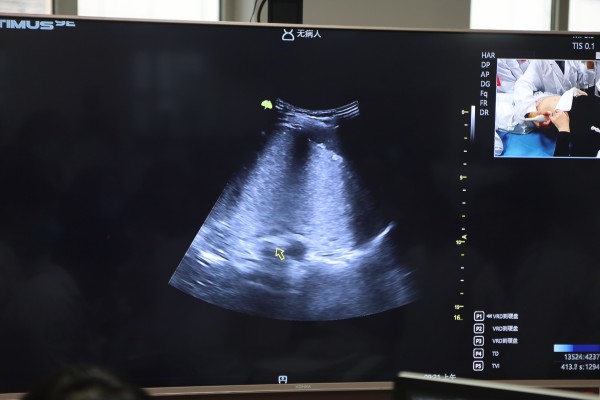

實(shí)操帶教環(huán)節(jié),辛集市中醫(yī)院王震、邢臺(tái)市第九醫(yī)院鈕世博、衡水哈勵(lì)遜國(guó)際和平醫(yī)院王文峰以及石家莊十二化建職工醫(yī)院岳素賓作為指導(dǎo)專(zhuān)家在現(xiàn)場(chǎng)進(jìn)行手把手實(shí)操教學(xué),從胃到食管(部分)、從小腸到結(jié)腸再到闌尾,從實(shí)用解剖到手法切面,系統(tǒng)詳盡地講解讓與會(huì)人員受益頗豐。為強(qiáng)化實(shí)操技能,培訓(xùn)班特別開(kāi)展夜間練習(xí)模式,進(jìn)行加餐訓(xùn)練。

理論授課環(huán)節(jié),北京大學(xué)人民醫(yī)院李建國(guó)教授、河北省第七人民醫(yī)院李獻(xiàn)亮主任醫(yī)師、甘肅蘭州中核五〇四醫(yī)院竇曉霞教授、天津市第三中心醫(yī)院周鐵教授、東莞市清溪醫(yī)院姚偉權(quán)教授以及河北友愛(ài)醫(yī)院馬海蘭教授從胃腸超聲現(xiàn)狀及未來(lái)提高方向,操作手法、臨床思維,充盈法超聲造影及超聲診斷等不同維度對(duì)胃腸超聲技術(shù)進(jìn)行講解,生動(dòng)詳細(xì)的理論講解、真實(shí)典型的案例分析讓與會(huì)學(xué)員收獲滿滿。